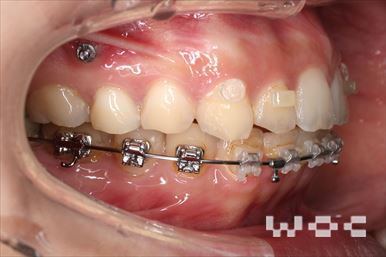

受け口・反対咬合上のみ舌側矯正、下はエッジワイズ装置

上は舌側矯正を希望。

上の叢生を改善することにより、受け口を改善。通院に協力が良く、舌側矯正であるが予定より短い期間で終了しました。-

- 年齢:30歳男性

- 主訴:受け口を治したい

- 基本矯正料金:1,035,000円

- 治療期間:1年9ヶ月

- 非抜歯